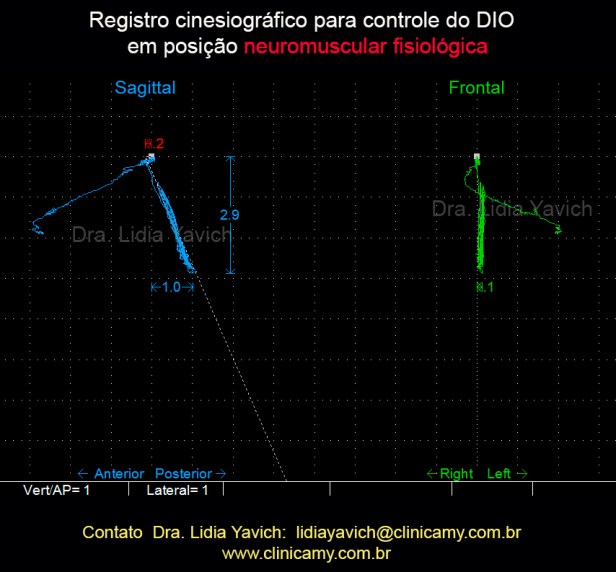

Os músculos mastigatórios da paciente foram desprogramados eletronicamente e foi registrada a posição de repouso com um cinesiógrafico computadorizado.

Os músculos mastigatórios da paciente foram desprogramados eletronicamente e foi registrada a posição de repouso com um cinesiógrafico computadorizado.

A paciente apresentava um espaço livre interoclusal patológico de 6,3 mm e uma retroposição mandibular de 0,5 mm.

Com o registro obtido com o cineciógrafo computadorizado foi confeccionado um dispositivo intraoral (DIO) para reposicionar tridimensionalmente a mandíbula.

Com o registro obtido com o cineciógrafo computadorizado foi confeccionado um dispositivo intraoral (DIO) para reposicionar tridimensionalmente a mandíbula.

A posição NEUROMUSCULAR FISIOLÓGICA, foi gravada sob a forma de um registro de mordida oclusal, que mais tarde foi utilizado para fabricar um DIO ( dispositivo intraoral)

Controle do dispositivo intraoral (DIO). ESTES CONTROLES SÃO FEITOS COM FREQUÊNCIA durante a primeira e a segunda fase do tratamento Modificando e aprimorando a POSIÇÃO NEUROMUSCULAR FISIOLÓGICA.

Controle do dispositivo intraoral (DIO). ESTES CONTROLES SÃO FEITOS COM FREQUÊNCIA durante a primeira e a segunda fase do tratamento Modificando e aprimorando a POSIÇÃO NEUROMUSCULAR FISIOLÓGICA.